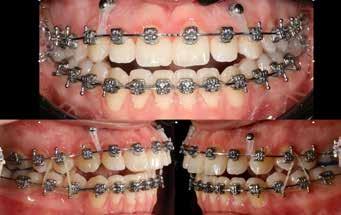

terséges harapásemelés pedig az alsó hatosokra, majd később a felső négyesekre került (8. kép). Az intermaxilláris elasztikus gumihúzás class-2-ess vektorú volt annak érdekében, hogy a disztálharapás korrekciója tökéletes legyen (9. kép). A harapást beállító elasztikus gumihúzásokat – mint minden kezelésnél –, ebben az esetben is folyamatosan, az egész kezelés alatt 24 órában (étkezések kivételével) viselte páciensünk.

A második Pitts-21 fix készülékes fázis ideje 16 hónap volt (10-12. képek)